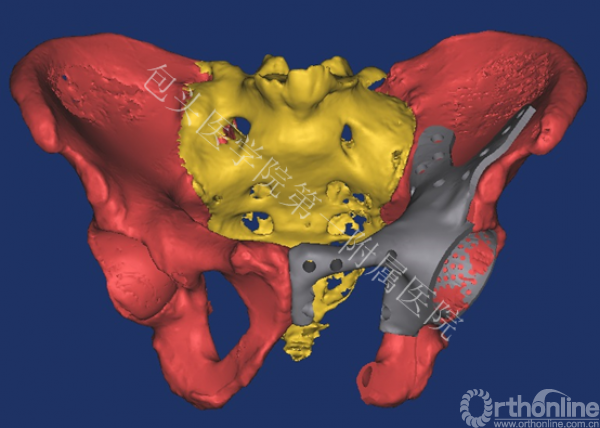

骨盆肿瘤切除后骨缺损的精细化解剖重建一直是世界性难题。传统的标准化假体仍存在诸多问题,如:无法满足不同缺损类型的重建要求,力学不稳定导致术后断裂,术后功能修复差距也很大。为此,董乐乐教授团队与西安交通大学机械制造系统工程国家重点实验室生物制造研究团队共同协作,经反复论证和数字化设计,经过3D打印为患者量身定制了个性化假体。

术前根据患者的CT数据,设计出解剖结构和肿瘤切除后与骨缺损部位完全匹配的假体,再应用“激光3D打印成形”制造出符合患者生理解剖和生物力学要求的钛合金金属假体。手术完整切除骨盆肿瘤,精确安放定制假体,达到良好的解剖和功能重建。最终,为患者提供精确化医疗和个性化医疗的服务。